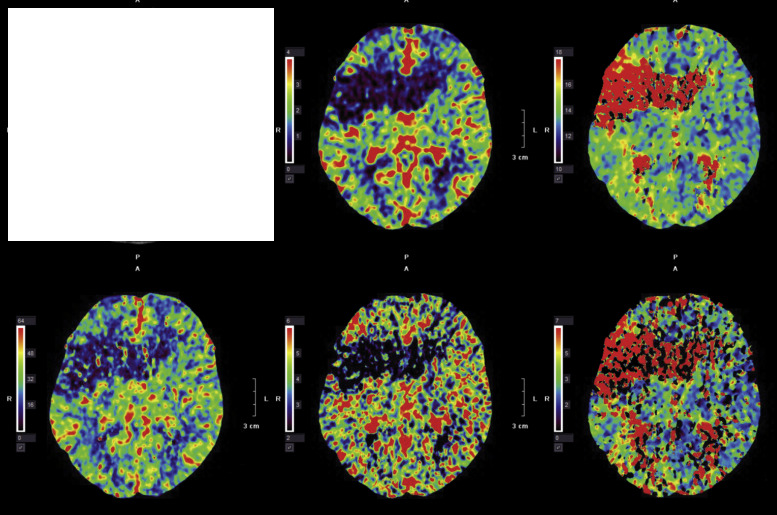

which type of imaging is this?

CT venogram

PET scan

CT angiography

CT perfusion

MRI